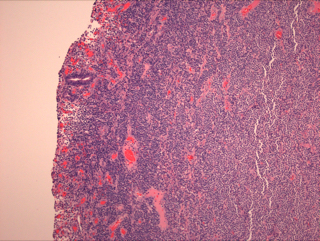

MEITL EATL 是一种原发性肠道淋巴瘤,来源于上皮内淋巴细胞。肿瘤由中等单一形态细胞组成,广泛浸润上皮,不伴其它炎性细胞,坏死也较少见。发病与乳糜泻无关。原为 2 型 EATL,WHO 2016 修改版将此型分出单独立为一类。

肿瘤细胞广泛侵润,具有明显亲上皮性,包括隐窝和表面肠上皮。肠绒毛变形、扩大。细胞中等大小,形态单一,核圆,染色质精细分散,无明显核仁,胞浆较淡相对较多。无混合炎性细胞,坏死也较 EATL 少。